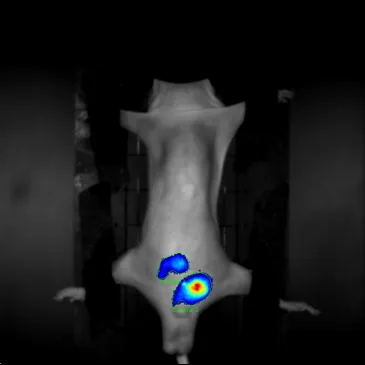

小动物三维光学活体成像设备凭借高空间分辨率与动态追踪能力,成为药物靶向性验证的核心工具,实现从“靶向设计”到“体内验证”的全流程可视化评估。在实验设计中,科研人员可采用“双标记”策略:通过荧光或生物发光探针标记药物载体(如纳米粒、抗体药物偶联物),同时用特异性探针标记靶组织(如肿瘤细胞表面抗原、病变器官特征蛋白)。设备通过同步捕捉两种信号的空间分布与强度关联,直观呈现药物在活体动物体内的迁移路径——从给药部位到血液循环,再到靶组织的富集过程被清晰追踪,明确药物是否精准“命中”目标,而非在正常组织中无差别分布。

“双标记”验证药物靶向性